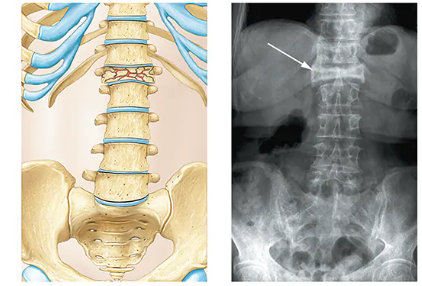

Comminuted